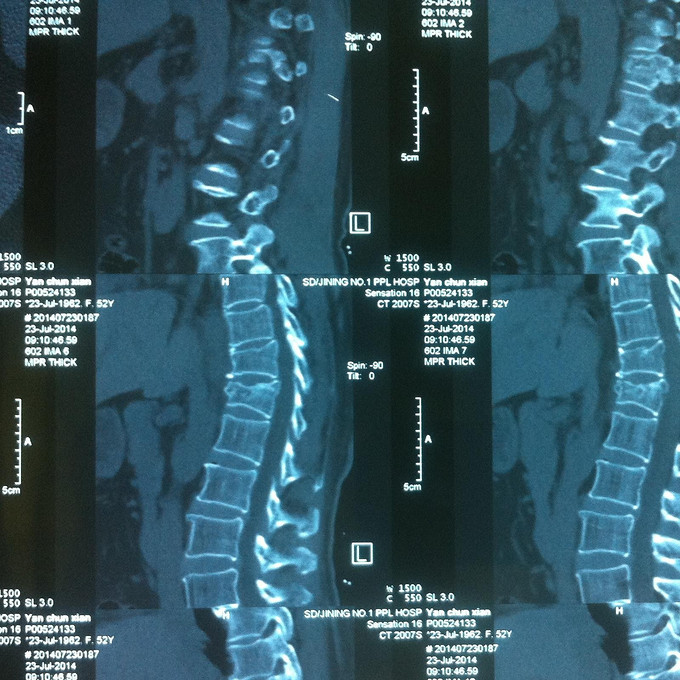

查体:腰部叩痛,腰部活动受限,双下肢感觉无异常,双侧屈髋、伸膝、踝背伸、踇背伸、跖屈肌肌力4-5级,双侧膝腱反射++,跟腱反射+,双侧巴氏征阴性, 影像学检查MR:腰椎骨折,累及中柱。

诊断:腰椎骨折 处理:1、完善相关辅助检查,明确诊断,有无手术指证; 2、患者拒绝行腰椎后路撑开复位内固定术;3、给予绝对卧床,在床上行腰部逐渐加软垫复位,配合促骨愈合、消肿药物。